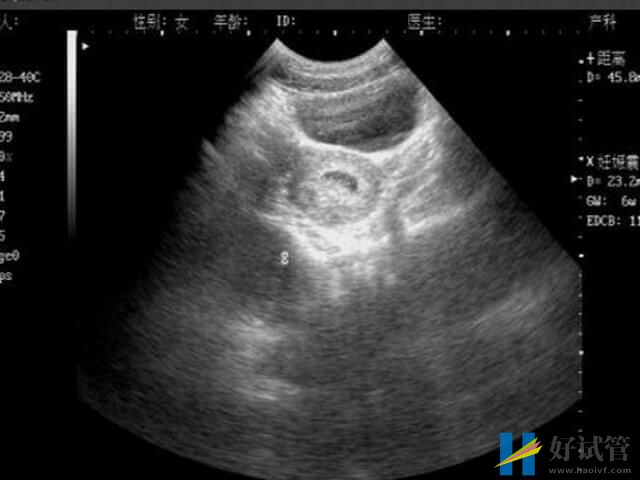

胎停在临床中称为胚胎停育,是指由于某种原因导致的胚胎停止发育,可进一步引起胚胎死亡。一般来说,胎停的发生概率最好的阶段就是怀孕早期的时候,其原因大致就如下所列:

当胚胎质量存在问题,如存在染色体异常等情况的时候,就容易导致怀孕早期的胚胎发育不完善的情况,此时有没有胎盘的保护,所以极易容易出现胎停的情况。

当胚胎着床不稳定的时候,随着怀孕天数的增加,体内分泌的hcg等激素也无法达到孕育胚胎生长所需,而得不到充足营养物质的胚胎,就有可能会发生胎停育的情况。

3、胎盘没形成